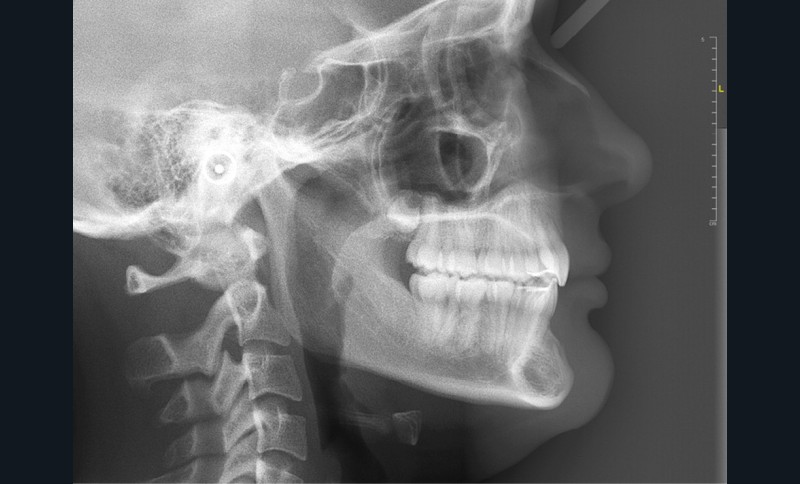

Les examens cliniques et radiologiques ont mis en évidence l’inclusion de 13 et 23, une légère classe II bilatérale par perte d’ancrage, un biotype parodontal de type IV de Maynard et Wilson avec une insertion du frein mandibulaire antérieur papillaire, une biproalvéolie et une typologie hypodivergente. La réalisation d’un examen tridimensionnel a permis de confirmer la localisation palatine de 23 et vestibulaire de 13 ainsi que de visualiser l’étendue des résorptions radiculaires touchant 12, 21 et 22 (fig. 1a-i).

Les résorptions radiculaires des dents adjacentes aux canines maxillaires incluses sont en effet fréquentes avec un risque plus important chez les femmes. La localisation sagittale de la canine incluse constitue un facteur de risque dans la présence de résorptions radiculaires [3]. Le recours aux examens tridimensionnels est donc indispensable dans le traitement de ces cas.